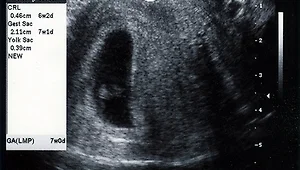

2003년 4월 3일 임신 7주째 2003년 4월 3일 임신 7주째 사진입니다. 2003. 12. 5.